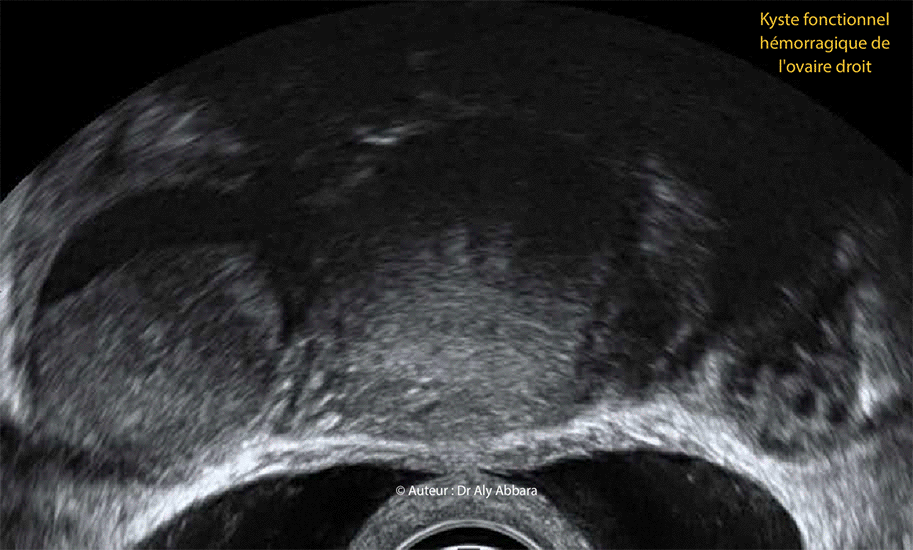

Kyste ovarien droi fonctionnel et hémorragique

Image animée montrant un des aspects échographiques d'un kyste fonctionnel et hémorragique

de l'ovaire droit disparaissant complètement à l'échographie de contrôle trois mois plus tard.

On observe nettement la présence, au sein de l'ovaire droit, d'une formation kystique uniloculaire, à paroi fine, sans végétations endophytiques, et à contenu comportant deux composantes, l'une anéchogène (niveau supérieur) et l'autre échogène (niveau inférieur) et sans vascularisation (aucun signal Doppler) ; il s'agit d'un caillot sanguin se déposant au fond de l'ovaire.